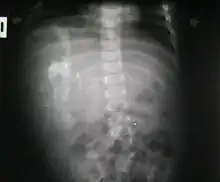

Fetus in fetu

Fetus in fetu (or foetus in foetu) is a rare developmental abnormality in which a mass of tissue resembling a fetus forms inside the body of its twin. An early example of the phenomenon was described in 1808 by George William Young.[1]